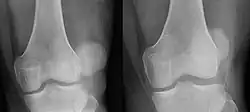

Patellar luxation on radiograph: Left before, right after reduction; after reduction, the patella is still displaced.